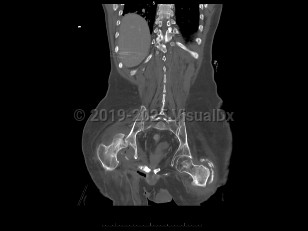

An infection of a joint most frequently caused by bacteria (although fungi, parasites, and mycobacteria may also rarely cause this infection).

Patients present with a swollen, warm, stiff, and painful joint. Fever may be present. The majority of the time, a single joint (usually the knee) is involved. Symptoms develop over 1-2 weeks. If the infection is caused by N gonorrhoeae, patients classically also present with a rash and tenosynovitis. If the infection is due to fungi or mycobacteria, the symptoms may be subtler and may worsen more gradually.

Diagnosis can be made by arthrocentesis. Joint fluid should be sent for analysis including cell count, microscopic analysis for crystals, Gram stain, and bacterial culture. Additional cultures of the joint fluid can be obtained if an atypical pathogen is suspected by history or examination.